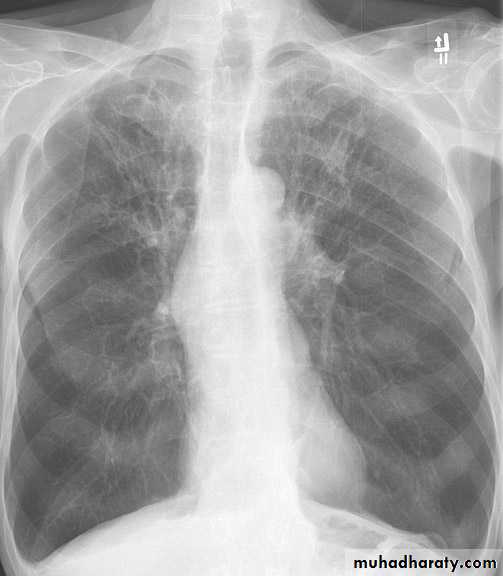

Miliary tb